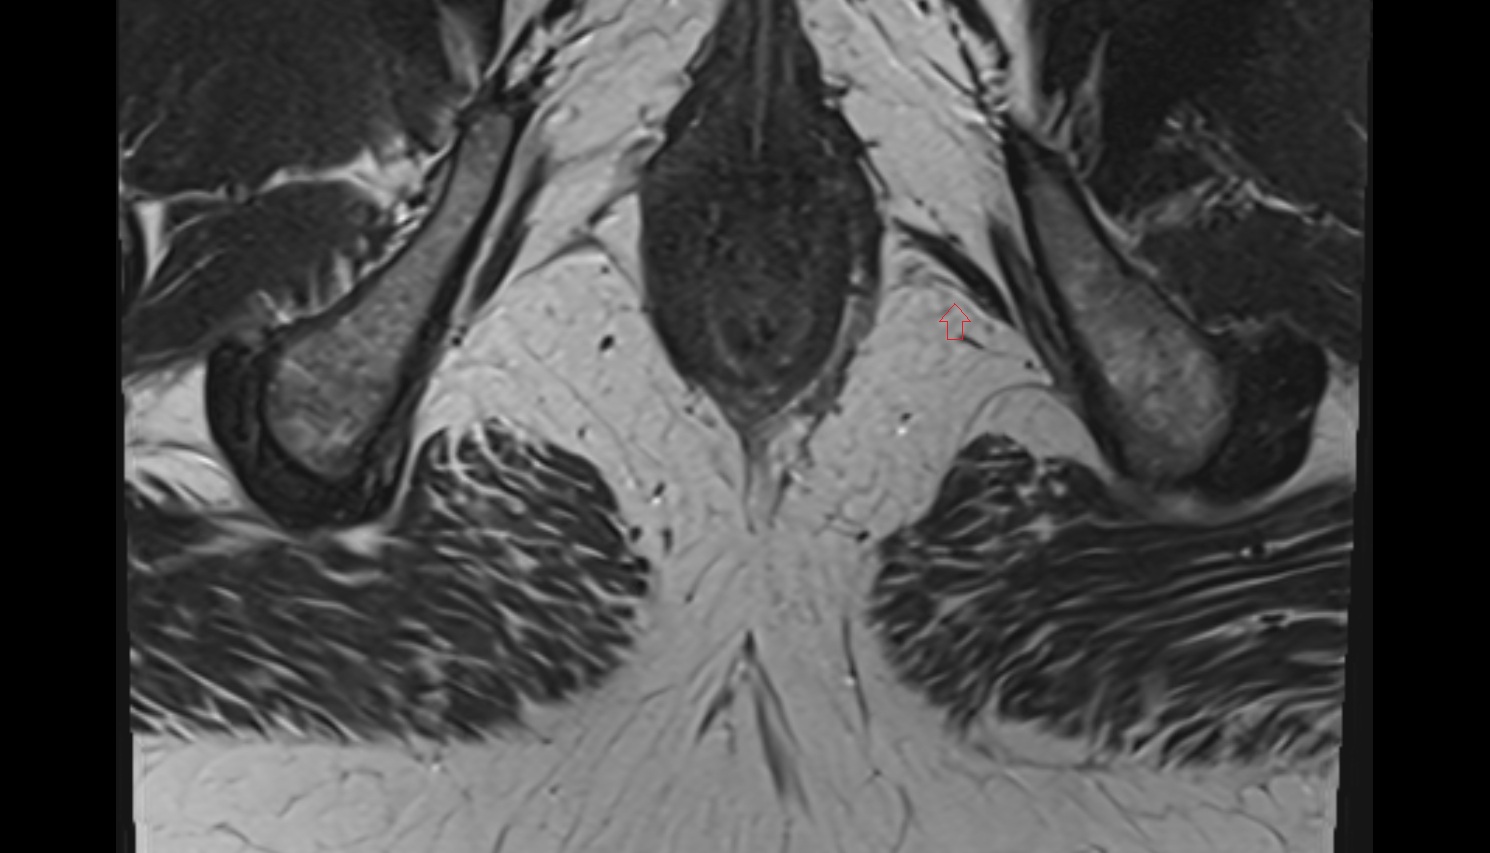

- Peripheral zone of prostate

- Anterior Fibromuscular Stroma of prostate

- Central zone of prostate

- Transitional zone of prostate